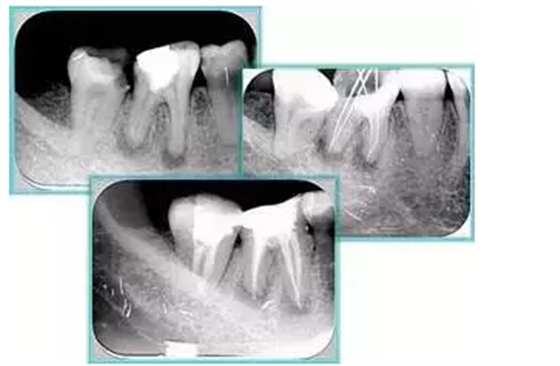

7. 器械折斷

右圖及下圖為器械折斷的 X 線片。箭頭處示折斷器械。

解決方法: ( 1 )取出。 ( 2 )通過。 ( 3 )重新確定工作長度,充填。 ( 4 )根尖手術(shù)。

器械折斷可以不用取出,取出的原因多是患者心理因素。留在里面的器械關(guān)鍵是進(jìn)行消毒,預(yù)防性使用抗感染藥物,預(yù)防感染。

二、臺階

定義:根管內(nèi)壁上人為產(chǎn)生的不規(guī)則形狀阻止器械順利進(jìn)入根尖。

原因:器械沒有預(yù)彎,根向壓力過大。

右圖箭頭處示臺階形成。

解決方法: ( 1 )器械預(yù)彎。 ( 2 )若出現(xiàn)銼的螺紋擰緊,立即換用小號銼。 ( 3 )一旦到達(dá)WL,即按照從小到大順序預(yù)備根管。 ( 4 ) H銼幫助提高切割效率。